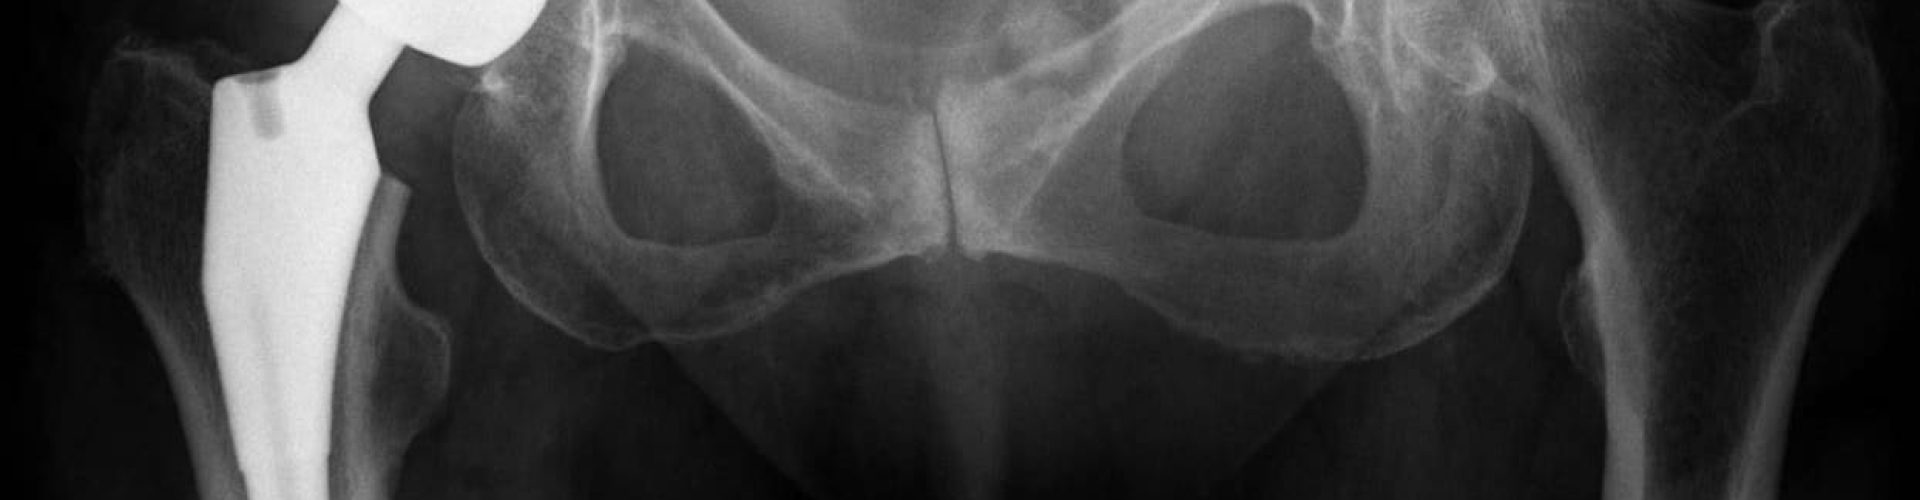

The problems with Stryker hip implants primarily stemmed from a specific model known as the Stryker Rejuvenate and ABG II modular-neck hip stems. These devices were designed to offer more flexibility and a customized fit for patients, but they ended up causing significant harm. The metal-on-metal design led to the release of metal ions into the bloodstream, causing metallosis, tissue damage, and a range of other health issues. Patients also reported symptoms such as pain, swelling, dislocation, and difficulty walking, all of which significantly affected their quality of life.